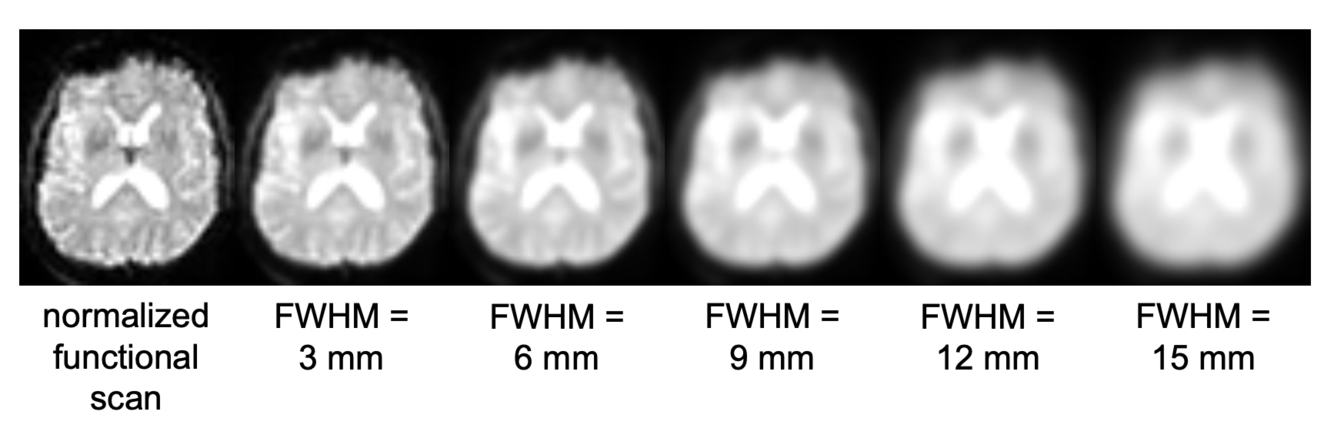

Spatial Preprocessing: Smoothing

Even after normalization, there is still a residual anatomical mismatch between participants. To account for this mismatch, the activation is smoothed so that activation in voxels close to each other become more similar. This also reduces measurement artefacts, and increases the signal-to-noise ratio

By convolution with a 3D gaussian kernel. This basically means that a “kernel” moves through all voxels and transforms the value of the voxel so that it is a combination of its own value and all the neighbouring values.

The value “Full width at half maximum” FWHM describes how large the kernel has to be. The larger the kernel, the more neighbouring voxels are taken into account when smoothing.

3 Arguments against smoothing

smoothing “enlarges” brains (into non-signal-voxels)

smoothing reduces the effective spatial resolution

smoothing can destroy fine-grained information